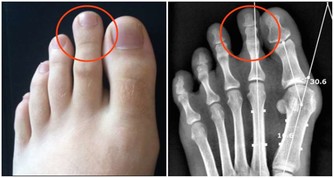

4、血管疾病。有些血管疾病比如常見於青年女性的雷諾病、大動脈炎,多發於中年男性的血栓閉塞性脈管炎,會影響人體末梢部位的供血。

4、按摩穴位。可按揉這四個穴位:心俞穴(兩肩胛骨中間、脊梁骨和兩側大筋部位)按揉36次,左右各轉18次;腎俞穴(即兩邊腰眼),兩側各按揉36次,每一側都是左右轉各18次,對促進腿部血液循環很有好處;揉搓湧泉穴,以感覺到熱為限度,再搓揉腳趾;特別是大腳趾頭第二節有幾根汗毛的地方,叫「三毛穴」,要多揉搓,然後稍用力捏3-5次。